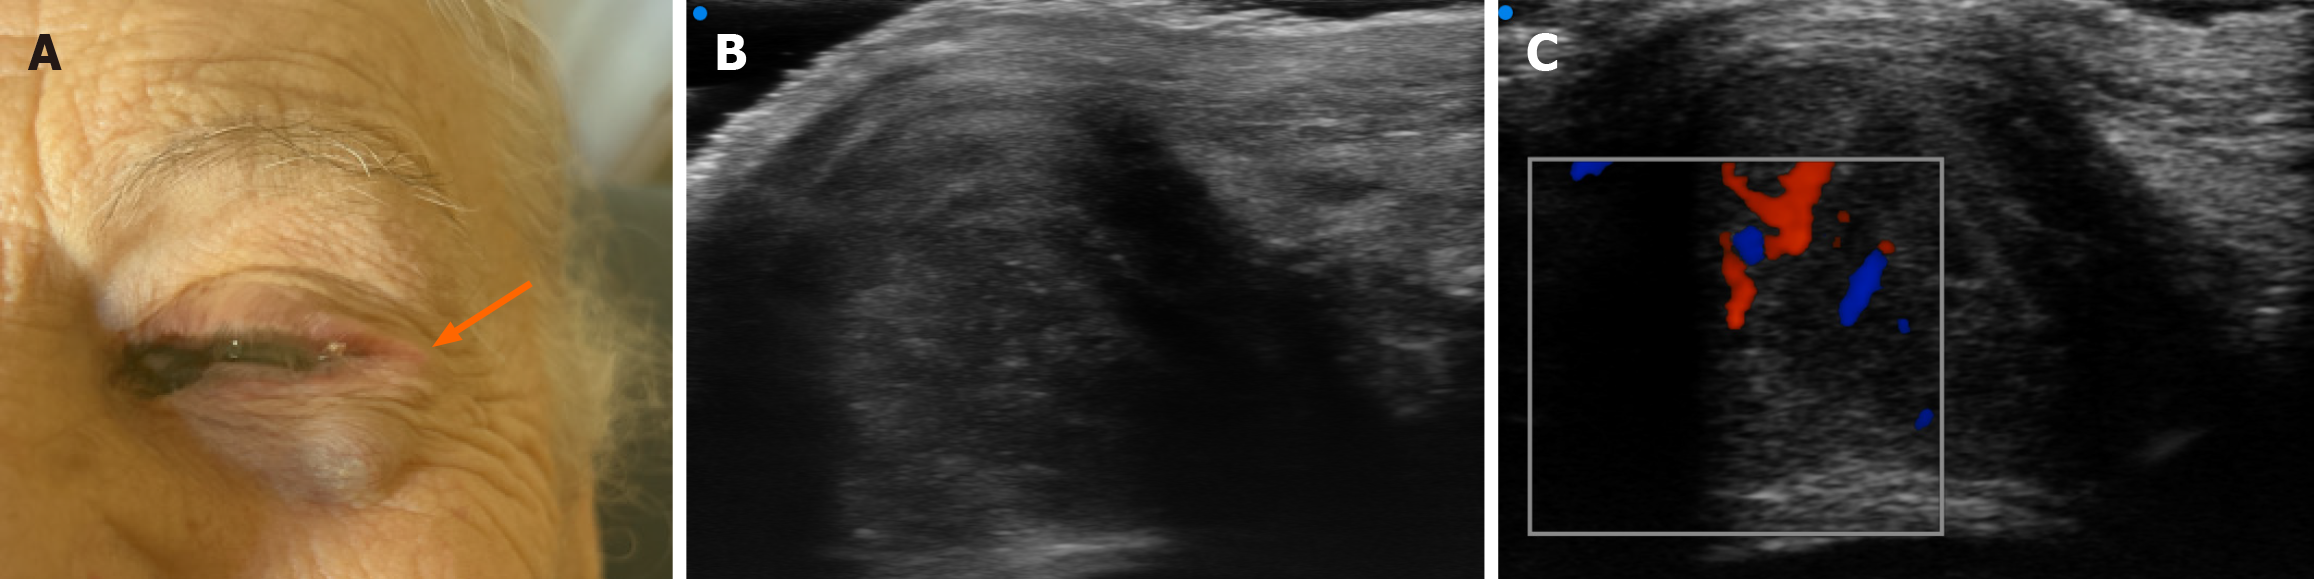

Figure 4 Multimodal evaluation of a subepidermal nodule in the lower eyelid, suspicious for conjunctival satellite metastasis.

A: Real-time clinical photograph with arrow indicating the anatomical location of the palpable lesion along the left lower eyelid; B: Ultra-high-frequency ultrasound image (48 MHz) showing a well-demarcated, hypoechoic subepidermal nodule (9 mm × 8 mm) with scattered hyperechoic foci; C: Color Doppler image revealing increased and accelerated perilesional vascularization, consistent with active neoplastic tissue.